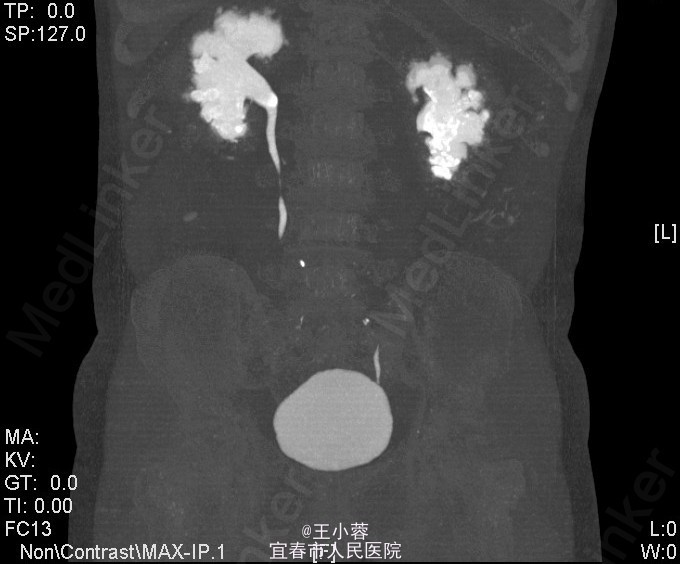

3、查体:未见明显异常 4、辅助检查:当地人民医院泌尿系彩超示:双肾多发结石(未见报告),我院肌酐124.2umol/L,糖6.62mmol/L。我院双肾CTU:1、双肾铸型结石,双肾中度积液,双肾功能减低;腹膜后多发稍大淋巴结。2、多囊肝,多囊肾,双肾多发复杂性囊肿。3、慢性胆囊炎。4、腹主动脉及双侧髂动脉硬化